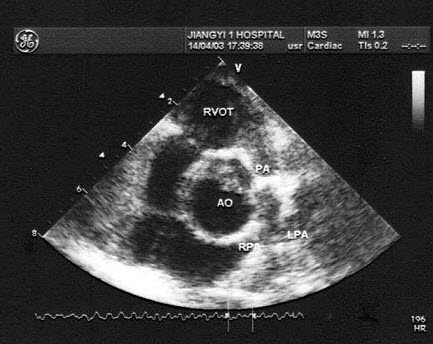

86、单项选择题

该病例最有可能诊断()

A.肺动脉内径增宽

B.动脉导管未闭

C.肺动脉瓣狭窄

D.肺动脉瓣关闭不全

E.右室流出道狭窄